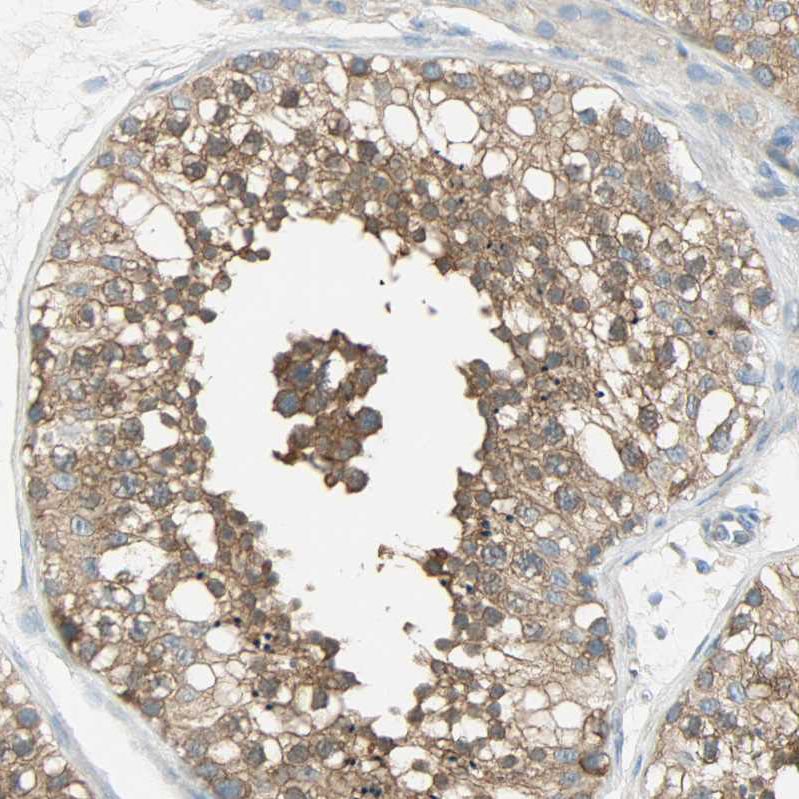

Immunohistochemical staining of human testis shows moderate cytoplasmic positivity in cells in seminiferous ducts.